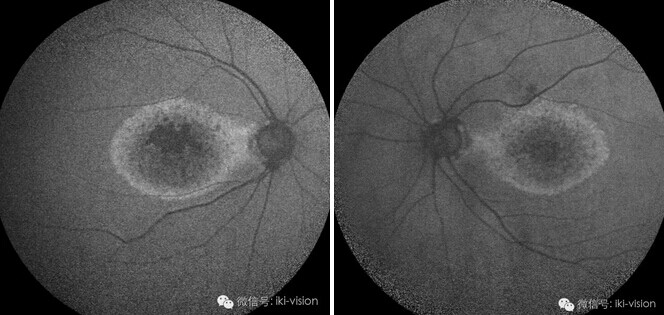

萎缩性AMD患者

2、自发荧光:可明显看到黄斑

部萎缩灶高荧光

3.OCT检查:右眼(上图)黄斑

中部IS-OS层光反射带消失,外

界膜破坏,RPE萎缩。左眼(下

图)大致同右眼

该患者诊断:双眼萎缩性AMD。

疑问:该患者右眼0.2,左眼0.3

的视力,黄斑中部弥漫性地图萎

缩(GA),OCT显示黄斑中部视

细胞层及RPE层萎缩,难以解释

患者右眼0.2左眼0.3视力。 于是